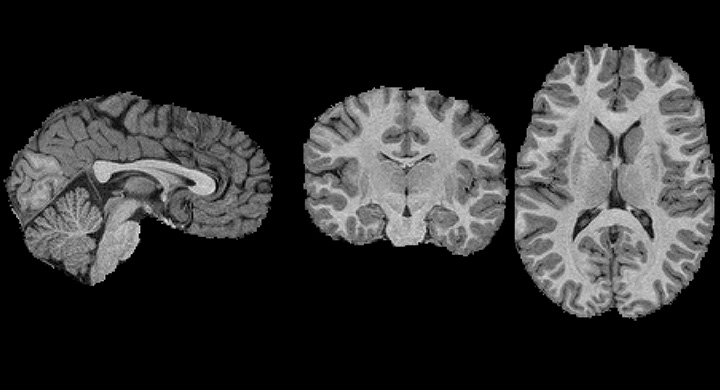

L'imagerie par résonance magnétique (IRM) est une technique d'imagerie médicale permettant d'obtenir des vues en deux ou en trois dimensions de l'intérieur du corps de façon non invasive avec une résolution en contraste relativement élevée. Cette technique fait l’objet d’améliorations permanentes grâce aux travaux de nombreux chercheurs dont Stenzel Cackowski et Aurélien Delphin, respectivement diplômés de Grenoble INP – Ensimag et Grenoble INP – Phelma, qui effectuent tous les deux un doctorat au Grenoble Institut des Neurosciences (GIN).

Pour comprendre, il faut rappeler que le principe de l’IRM consiste à envoyer des impulsions d’ondes électromagnétiques (radiofréquences, RF) dans le corps des patients. L'énergie de ces ondes RF est captée par les atomes d'hydrogène présents dans les tissus (ils entrent en résonnance). Cette énergie est ensuite libérée sous forme d'un signal observable. « Tous les atomes ne restituent pas leur énergie de la même façon en fonction de l'endroit où ils se trouvent : eau, matière plus dure, etc. On utilise également des champs magnétiques pour guider ce phénomène afin de modifier le signal selon nos besoins. » Chaque « séquence » (trains d’impulsions RF et de champs magnétiques) permet d’obtenir une image qu’il faut ensuite traduire en paramètres biologiques.

De son côté, Stenzel Cackowski, qui effectue sa thèse dans le cadre d’un financement par le MIAI*, travaille sur le diagnostic des déficiences intellectuelles chez l’enfant par imagerie. Pour cela, il étudie des données provenant de différents centres, ce qui le place face à une première difficulté. « Si une même personne fait une IRM sur deux sites différents, les images obtenues ne seront pas les mêmes, rendant difficile toute comparaison des données entre elles, explique le jeune chercheur. Avant toute chose, il est donc nécessaire de se débarrasser du bruit intrinsèque à chaque machine et algorithme de traitement d’image. »

Pour y parvenir, Stenzel développe des outils d’intelligence artificielle visant à harmoniser les images produites par les IRM. « Les histogrammes d’intensité des scans, par exemple, qui répertorient les valeurs apparaissant le plus souvent, doivent être les mêmes d’une machine à l’autre. » Une fois que cela sera fait, le jeune chercheur se concentrera sur la détection de déficience du développement intellectuel d’enfants à partir d’anomalies anatomiques (volumes, épaisseur des tissus …) en fonction de leur âge. Mais les outils d’harmonisation des images pourront être appliqués à bien d’autres types d’imagerie médicale : scanner, radio… A suivre !